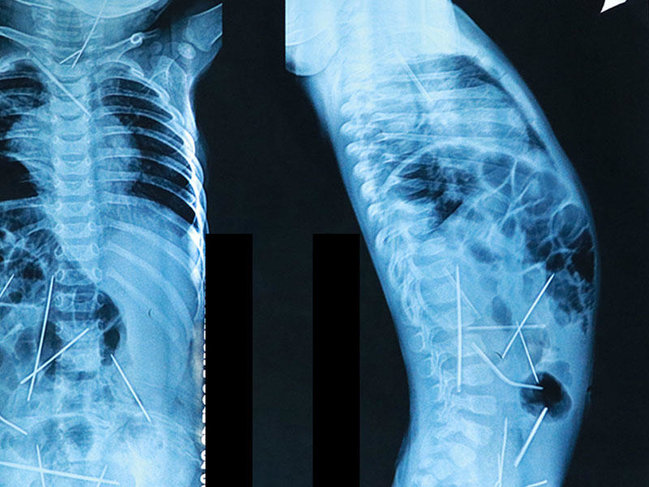

Özbəkistanda cərrahlar 9 saat davam edən cərrahiyyə əməliyyatı sayəsində 11 aylıq körpənin bədənindən 13 iynə çıxarıblar.

Professor Həbibulla Akilovun dediyinə görə, uşağın bədənində 3 iynə qaldığından təkrar cərrahiyyə əməliyyatı olacaq.

"Müayinə və analizlər zamanı bəlli oldu ki, o iynələr uşağın bədənində ən azı bir ay qalıb. İynələrin uşağın bədəninə necə düşdüyünün səbəbini hələlik bilmirik", - H.Akilov deyib.

Həkimlərin dediyinə görə, uşaq iynələri uda bilməzdi. Kimsə o iynələri uşağın bədəninə yeridib.